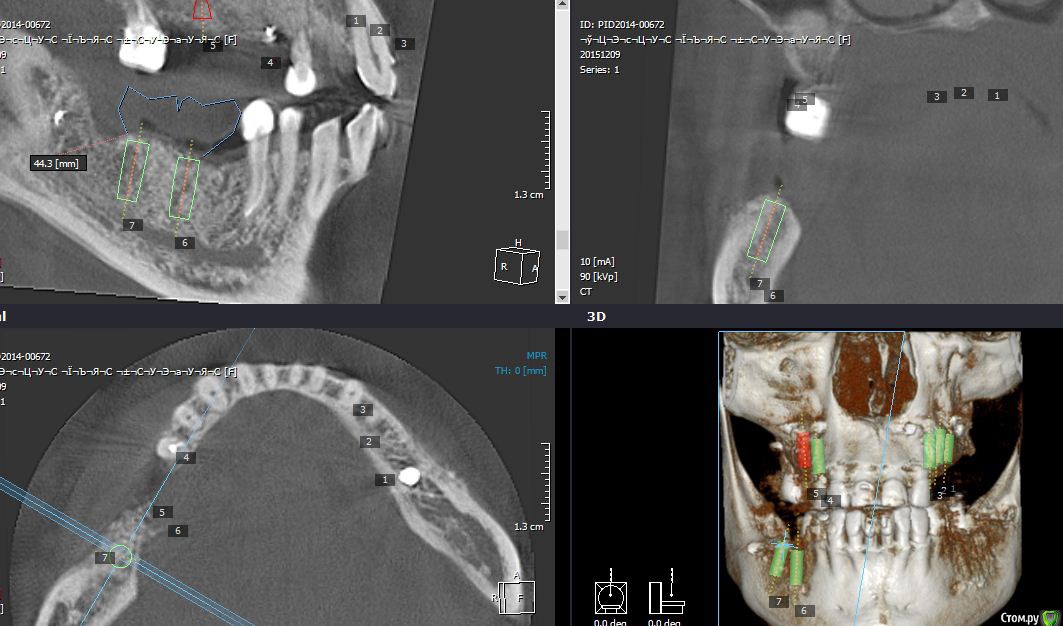

Endorphin Опубликовано 8 декабря, 2015 Автор Поделиться Опубликовано 8 декабря, 2015 Пора КТ показать. Завтра у пациентки запланирован синус, как раз сделаю контрольную кт. Ссылка на комментарий

Endorphin Опубликовано 21 декабря, 2015 Автор Поделиться Опубликовано 21 декабря, 2015 Пора КТ показать. Изначально рассчитывал на большее, но на фоне осложнений, думаю, и это хороший результат. Имплантата в позиции 46 так дистально расположен именно из-за недостатка кости. В январе-феврале установка. Ссылка на комментарий

Endorphin Опубликовано 30 января, 2016 Автор Поделиться Опубликовано 30 января, 2016 Сделайте фото когда ставить будете, очень интересноСделал.Результат превзошел ожидания. Из-за изначально неправильного расположения мембраны и графта, "ширина" начинается лишь отступя 6.5 мм от шейки 45, так что центр платформы дистализирован для моляра (8.5мм когда хочется 6мм). Качество фото так себе, но суть, думаю, ясна - кость наросла в достаточном объеме и качестве, торк > 45. Обязательно ССТ под швы. Еще раз всем спасибо! 1 Ссылка на комментарий